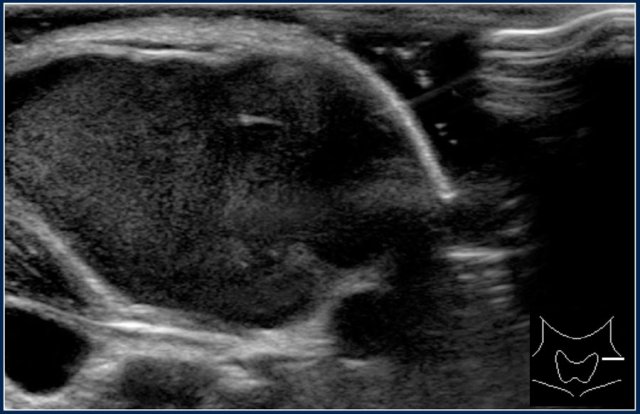

Here an ultrasound image of a six-year-old girl with a sudden swelling in the left neck.

There were several small anechoic cysts and one large cyst containing internal echoes, which were probably the result of a bleeding in a preexistent lymphangioma.